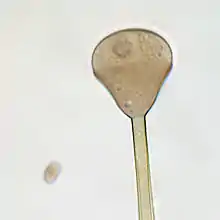

Apophysomyces variabilis resembles the other three members of the genus Apophysomyces but is characterized by the variable appearance of its sporangiospores and sporangiophores which range from club-shaped to trapezoidal to flattened spheres. The sporangiophore can measure up to 400 μm in length and has a funnel-shaped apophysis or swelling below the columella. Hyphae are smooth-walled, aseptate, and branched.[4]